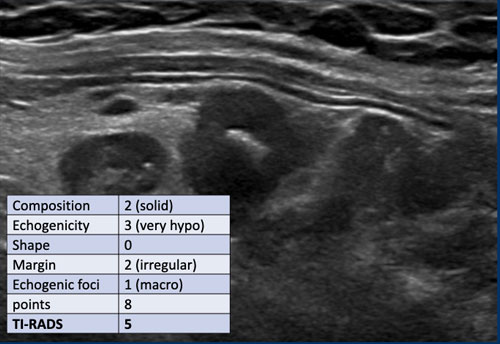

Ca 2

Xem hình ảnh và xác định điểm TI-RADS.

Cuộn hình ảnh để xem điểm TI-RADS.

Tiến hành phân tích bên dưới.

Điểm TI-RADS: 1 điểm cho sự hiện diện của vôi hóa thô.

Tổn thương này được phân loại TI-RADS 5, chủ yếu do tính chất giảm âm rõ rệt.

Nếu tổn thương có chiều cao lớn hơn chiều rộng, điều này sẽ cộng thêm 3 điểm.